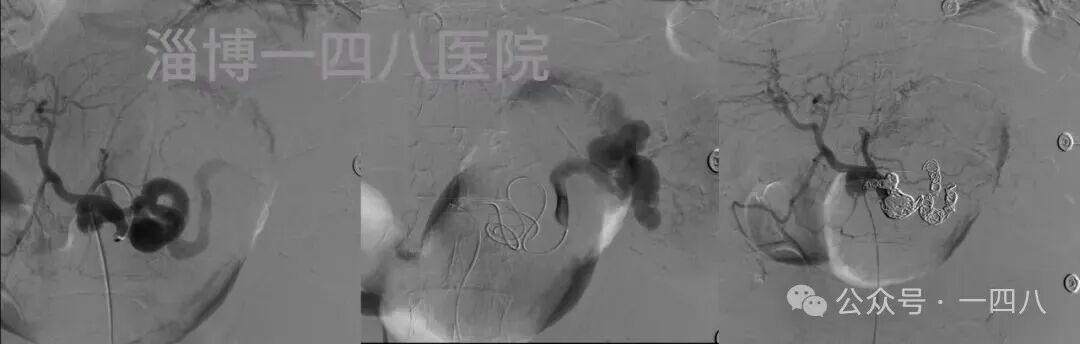

脾动脉瘤被称为“腹腔内不定时炸弹”,破裂后死亡率极高。患者到院立即启动绿色通道,多学科紧急会诊后,张希全教授团队决定立即行介入栓塞术。在DSA引导下,团队精准释放弹簧圈完成栓塞,成功止住出血。术后患者生命体征迅速平稳,血压回升,脱离生命危险,在介入血管科医护人员的精心照料下,目前恢复良好。